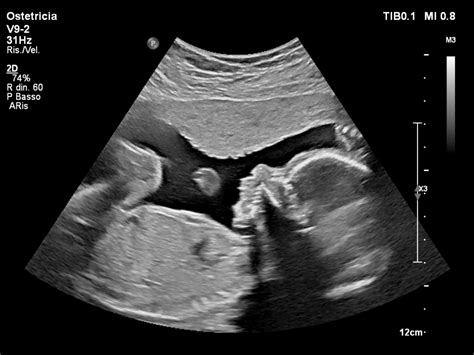

In alcuni casi, l'aborto spontaneo si manifesta senza alcun sintomo, ovvero senza perdite di sangue né dolori. Questo tipo di aborto, definito aborto silente o aborto mancato, si verifica quando il feto smette di svilupparsi senza che ci sia alcun segno esterno. In questi casi, la diagnosi è clinica e fondamentale con un controllo mediante ecografia, capace di accertare l’assenza del battito cardiaco nel feto. Il medico può sospettare un aborto mancato se l’utero non si espande progressivamente o rilevarlo durante un’ecografia prenatale di routine.

Se si manifestassero perdite di sangue e/o dolori, a prescindere dalla quantità, è importante contattare la propria Ginecologa il prima possibile per avere istruzioni e una valutazione professionale. La Ginecologa effettuerà una visita ginecologica ed un’ecografia per via transvaginale per controllare se l’embrione è presente nell’utero e per valutare la presenza del battito cardiaco fetale. In alcuni casi, è possibile che la Ginecologa ti chieda di effettuare un esame del sangue per misurare le quantità di beta-HCG (gonadotropina corionica umana), una sostanza che viene prodotta dalla placenta e aumenta costantemente fino al terzo mese di gravidanza. Un livello scarso o decrescente di beta-HCG possono significare la perdita della gravidanza. Un dosaggio delle beta può aiutare a capire.